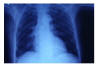

Fibrosis pulmonar. ICC.